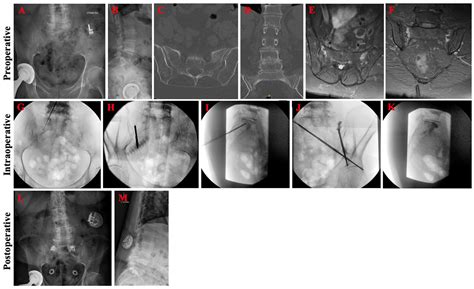

Diagnostic Approaches

Diagnosing an SIF requires a high index of suspicion from healthcare providers, as standard X-rays often miss these fractures, especially in the early stages. More advanced imaging is typically necessary to confirm the diagnosis.

💡 Note: In cases where conservative measures fail, or if the pain is debilitating, specialized procedures like sacroplasty—where bone cement is injected into the sacrum—may be considered by a qualified specialist.